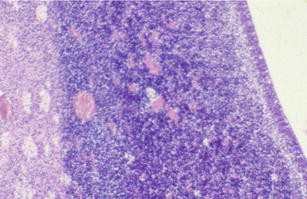

Jellinger G (1986) Anatomopathology of nontumoral aqueductal stenosis. J Neurosurg Sci 30:1–16